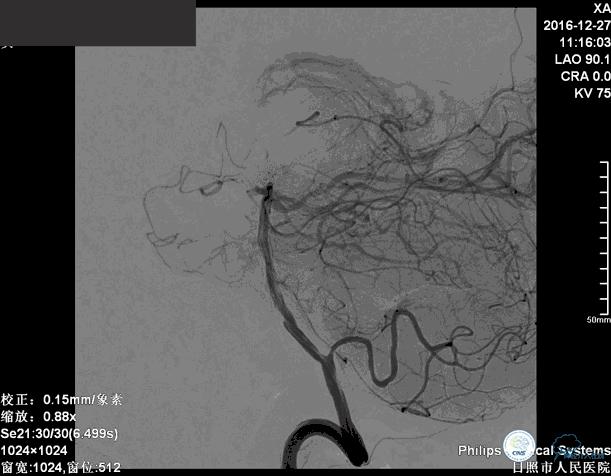

确诊:基底动脉顶端宽颈未破裂动脉瘤,动脉瘤大小约6mm×9mm,瘤颈约4毫米。

分别选择了7mmx30cm、6mmx30cm、2个4mmx15cm、3mmx8cm、2mmx8mm Target共6个弹簧圈进行栓塞。

术后

术后患者神志清楚,术后肢体运动较术前未见明显异常。

这个手术的难点是在保证动脉瘤致密栓塞的同时,要保证双侧大脑后动脉的通畅。最终手术达到了较好的效果。

术后患者神志清楚,术后肢体运动较术前未见明显异常。双微管技术降低了患者治疗的费用。同时避免了支架置入以后,终生服用抗血小板药物的情况。